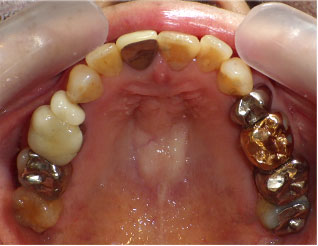

- ブリッジ 症例写真 B-0004スタンダードジルコニア(A)16本・レジン充填5本・抜歯6本 男性モニターの方です。

Before

After詳細はコチラ

スタンダードジルコニアクラウン法による虫歯治療の症例写真

施術 スタンダードジルコニア(A)16本・レジン充填5本・抜歯6本 - コメント

この方は虫歯が進んでしまっていて、抜歯が6本必要でした。

歯科治療恐怖症で虫歯治療に行けなかったとの事でしたので、

1回目は無痛麻酔での治療を行いました。無痛麻酔は最初の1回だけでした。

歯科医師との信頼関係が構築でき、無理なく痛みがない治療をすることで、

根の治療や歯型取りなどは無痛麻酔を使わなくても治療する事が出来ました。

抜歯となった部分の両側に歯がありましたのでブリッジでの治療をする事が出来ました。

まだお若い方ですので入れ歯は避けたいですし、両隣に残った歯も虫歯で

治療が必要でしたのでブリッジで治療を選択しました。

治療前後のお写真を比較しますと、ご自身の歯もとてもきれいになっています。

治療の際には歯石除去や歯磨き練習を行う事で、歯だけではなく歯茎もきれいになりました。

この方は根の病巣の手術が必要でしたので、通常よりも治療回数が多く全部で10回でした。